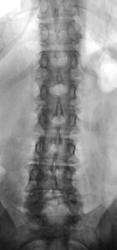

Боли в пояснице.  Пациент направлен на рентгенографию поясничного отдела позвоночника.

Очтеохондроз, 4 период.

Остеохондроз, грыжа Шморля L3. Возможно старый перелом. А, что за понятие остеохондроз 4 период. Иногда пишут стадии. Такое разграничение где-то написано?

Грыжа L3-L4

Остеохондроз, Грыжа Шморля Л2-3 диска, S-образный сколиоз

Контур и структура передней поверхности L3 в сочетании с превертебральными сосудистыми кальцинатами на этом уровне позволяют заподозрить аневризму брюшной аорты

Да, Вы правы аневризма брюшной аорты есть, она диагностирована ранее.

о тож, расслаивающая или воспалившаяся аневризма проявляет себя как раз болями в пояснице. Это уже несколько серьезнее остеохондроза